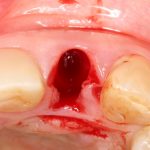

После потери зубов с альвеолярным гребнем происходит ряд серьезных изменений. Утрата функции ведет к изменению микроциркуляции крови в области удаления, а воспалительные явления (из-за чего, собственно, удаляются зубы) еще больше усугубляют этот процесс. Как результат, оставшиеся без зубов и трофики участки альвеолярного гребня начинают меняться в форме и объемах, т. е. атрофироваться. Причём, атрофия челюстей после удаления зубов происходит всегда и у всех, разница лишь в её степени:

Разумеется, мы можем на неё влиять. Так, немедленная имплантация и превентивная аугментация лунки уменьшают степень атрофии, хотя и не предотвращают ее полностью:

Так вот, чрезмерная атрофия альвеолярного гребня может лишить нас возможности имплантации — нам просто не хватит объемов костной ткани для нормальной установки имплантов. Однако, эта проблема решаема — существует целый ряд методик остеопластики (включая синуслифтинг), позволяющих восстановить любой объем костной ткани в в любом участке зубного ряда с высокой степенью эффективности. И, как правило, хорошие врачи в хороших клиниках так и поступают: